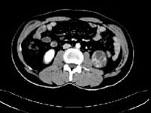

问题 女,63岁,左腰部隐痛不适1个月余,CT平扫+增强如图所示,下列哪项诊断正确 ( )

选项 A、左肾下极脓肿 B、左肾下极淋巴瘤 C、左肾下极错构瘤 D、左肾下极癌 E、左肾下极囊肿

答案 D